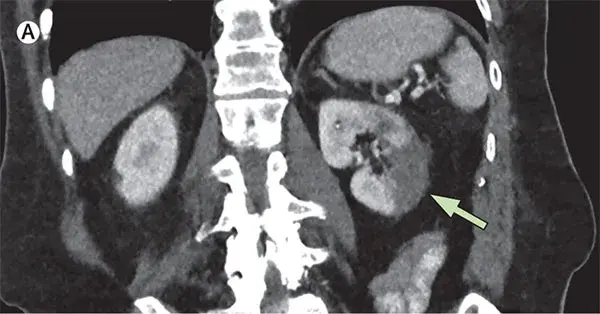

Main Trial: Micofenolato para Nefropatia por IgA

Main Trial: Micofenolato para Nefropatia por IgA

O tratamento da Nefropatia por IgA está longe de ser simples, confere o Trial mais recente que avaliou eficácia do Micofenolato.